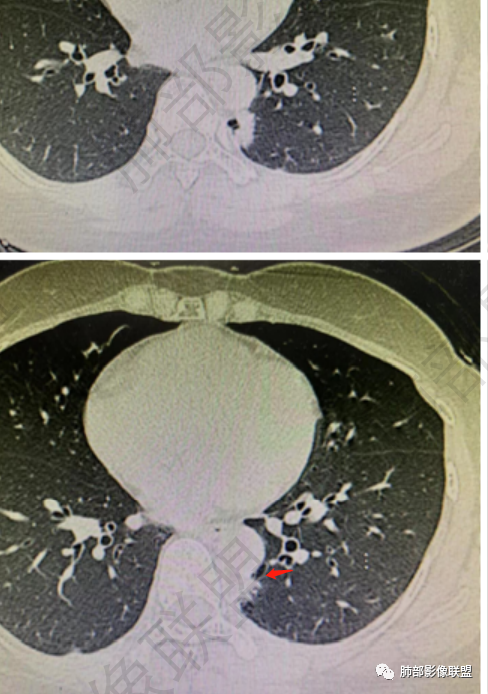

女性,体检发现,右肺上叶后段麿玻璃影!考虑AAH,左肺下叶病灶,外有毛刺伴囊腔样改变,考虑腺癌可能性大。

左肺下叶胸膜下不规则结节,边界清,短毛刺及囊腔,支气管扩张,邻近胸膜增厚,右肺上叶磨玻璃结节,边界清,考虑左肺下叶腺癌,右肺上叶AIS,鉴别炎性结节。

左肺下叶胸膜下结节,呈不规则型,边缘分叶、毛糙,内囊腔可见分隔,考虑腺癌,鉴别隔离症,右肺上叶磨玻璃结节,建议随诊。

左下叶脊椎旁:囊实性

看纵隔窗:实性成分密度不高,囊张力高,内有间隔,偏胸膜侧,实性部分内部支气管聚集。

实性区域边缘平直、凹陷

首先囊的位置?为啥没考虑是空洞?空洞张力偏低一些,一般在中央一些,所以不太支持,纵隔侧几乎无壁,不太支持空洞。

囊实性?这部位,第一印象要警惕--隔离症

1、右肺上叶混合密度磨玻璃结节特征性较强,尤其是后段病灶,边界清楚,应高度警惕微浸润腺癌,这个不用纠结,我们可以等,定期复查行之有效。

左肺下叶背段脊柱旁病灶相当不规则,形态既不符合空洞,也未能围成一完整的囊圈影,未见典型的分叶、毛刺及清楚的磨玻璃晕,前方出入支气管轻度扩张,纵隔窗病灶密度偏高不均,临近胸壁未见侵入。双肺门及纵隔未见增大淋巴结。

客观评价,该病灶缺乏恶性肿瘤影像学特征,尽管我们不能排除恶性。

结合本病例:年轻女性患者,体检发现病灶。影像学表现为左下肺类囊腔样结节,整体边界清楚,实性区域边缘平直、凹陷,缺乏典型分叶毛刺、胸膜改变等,病灶也未显示清楚的磨玻璃勾边,病灶不大而肺门纵隔未见肿大淋巴结,综合考虑慢性炎性肉芽肿可能性较大。必要时可结合病理检查。